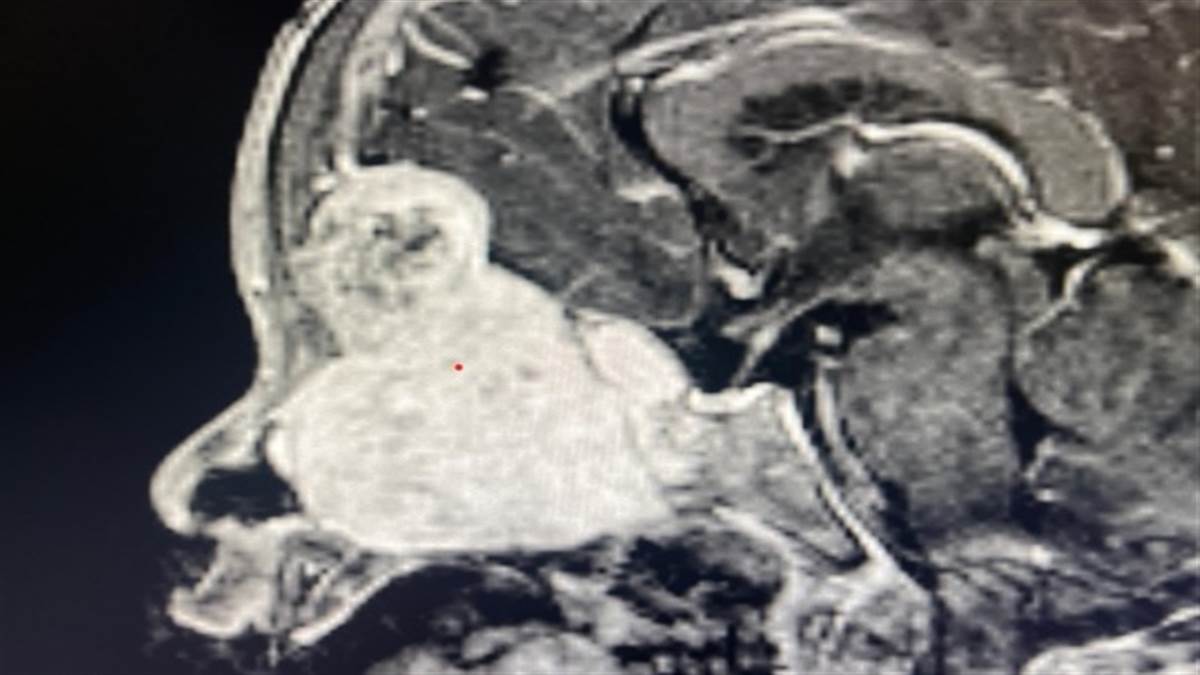

ਬੱਚੇ ਦੀ ਖੱਬੀ ਅੱਖ ਬਾਹਰ ਨਿਕਲ ਆਉਣੀ, ਅੱਖ ਦੀ ਮੂਵਮੈਂਟ ਰੁਕ ਜਾਣੀ, ਸਾਹ ਲੈਂਦੇ ਸਮੇਂ ਘਬਰਾਹਟ , ਨੱਕ ਵਿੱਚੋਂ ਮਾਸ ਦਾ ਟੁਕੜਾ ਦਿਸਣਾ ਅਤੇ ਅੱਖ ਵਿੱਚੋਂ ਲਗਾਤਾਰ ਪਾਣੀ ਆਉਣ ਵਰਗੀਆਂ ਗੰਭੀਰ ਸਮੱਸਿਆਵਾਂ ਸਨ। ਜਾਂਚ ਦੌਰਾਨ ਸੀਟੀ ਸਕੈਨ ਅਤੇ ਐੱਮਆਰਆਈ ਨਾਲ ਪਤਾ ਲੱਗਿਆ ਕਿ ਬੱਚੇ ਦੇ ਨੱਕ, ਸਾਇਨਸ, ਅੱਖ ਅਤੇ ਦਿਮਾਗ ਤੱਕ ਫੈਲਿਆ ਲਗਪਗ 7 ਸੈਂਟੀਮੀਟਰ ਦਾ ਟਿਊਮਰ ਹੈ। ਬਾਇਓਪਸੀ ਵਿੱਚ ਇਹ ਟਿਊਮਰ ਮੇਨਿੰਜੀਓਮਾ ਨਿਕਲਿਆ, ਜੋ ਬੱਚਿਆਂ ਵਿੱਚ ਬਹੁਤ ਹੀ ਦੁਰਲੱਭ ਹੁੰਦਾ ਹੈ।